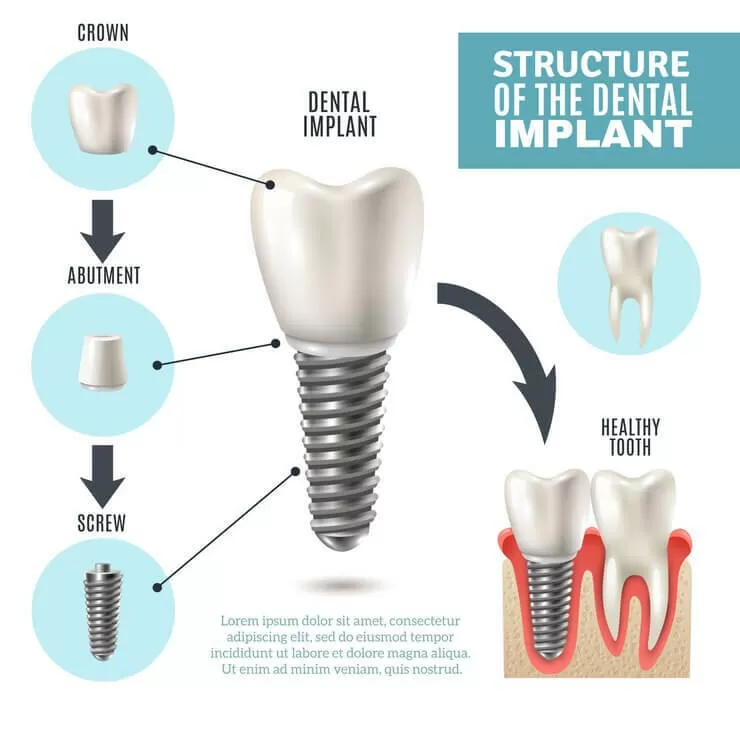

Конструктивное строение

Искусственные корни бывают разборные и неразборные (цельные).

Неразборные состоят из внутрикостной части в виде винта либо пластины, которая переходит в головку (при установке выступает над поверхностью десны). При вживлении такого импланта допускается немедленная установка коронки или протеза.

Разборный имплант состоит из нескольких элементов:

- металлический стержень — аналог зубного корня, который устанавливают в челюстную кость;

- заглушка — защищает внутреннюю полость стержня от врастания тканей в период остеоинтеграции;

- формирователь десны — придает десневому краю эстетический вид (ставится в среднем на 2 недели);

- абатмент — часть, выступающая над десной, которая соединяет основу и коронку;

- коронка — аналог натурального зуба.

Элементы соединяются между собой винтовой резьбой, цементом или методом вклинивания.

Главное преимущество разборной конструкции — если придется поменять коронку или протез, не потребуется удалять стержень из кости, достаточно будет заменить только верхнюю часть.